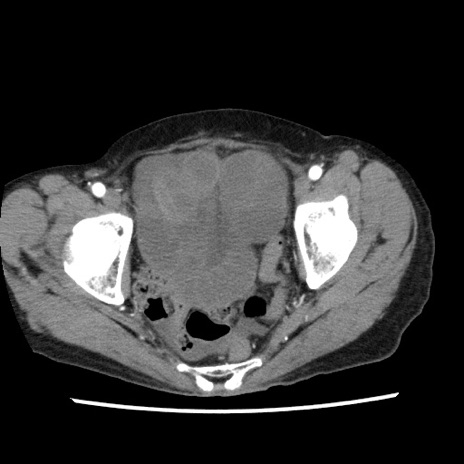

矢状断像

【症例】80歳代女性

【主訴】腹痛

【現病歴】8時間前から腹痛あり来院。

【既往歴】糖尿病、脂質異常症、子宮体癌にて子宮全摘術

【身体所見】意識清明・会話良好だが腹痛で苦悶様、全腹部にわたって反跳痛と圧痛あり

【データ】WBC 13600、CRP 0.14、LDH 224、CK 90